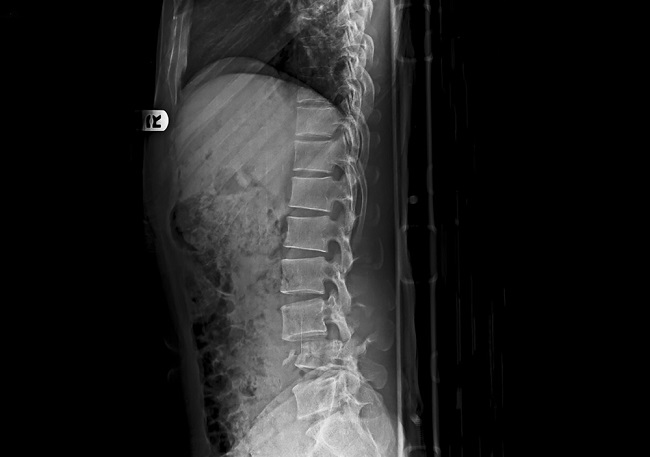

Diagnosis fraktur dan dislokasi tulang belakang dapat dilakukan melalui anamnesis, pemeriksaan fisik dan pemeriksaan penunjang. Penting untuk selalu mencurigai adanya cidera tulang belakang pada pasien trauma sampai diagnosis cidera tulang belakang ditegakkan. Pemeriksaan penunjang yang dapat dilakukan adalah pemeriksaan radiografi polos, CT-scan dan MRI.[5]